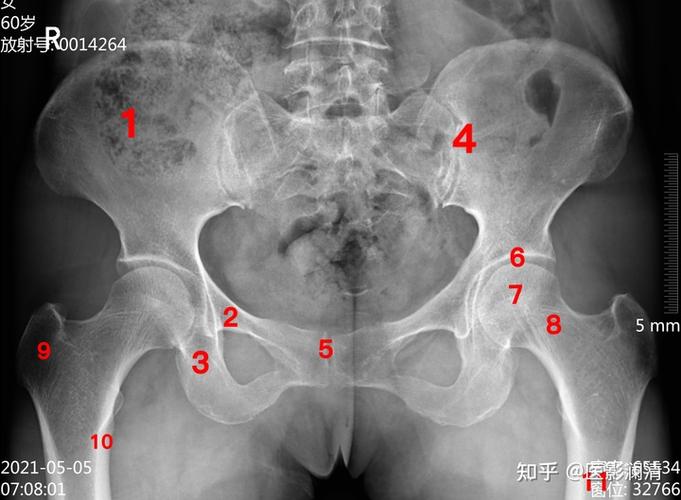

正常骨盆正位片x线解剖